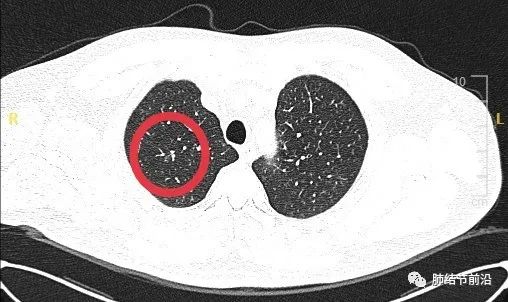

33岁男性,首次发现右上肺实性结节11mm,吸烟史,无家族史,CT如下。

主要还是看CT影像。首先看边界,有典型的边界毛糙,短毛刺,这个是肺癌的特征性表现。

并且,结节分叶很深。

根据这两个关键影像学特点,需要高度怀疑肺癌,而且为恶性程度较高的腺癌。